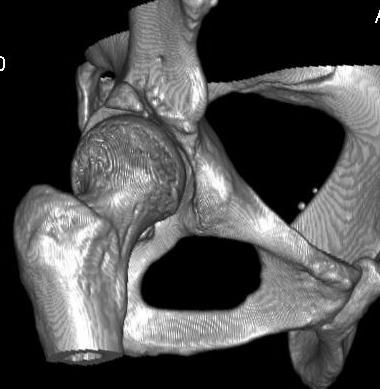

Добавляю снимков для "информационной поддержки принятия решения" (ну, нравится мне это выражение )). Поступило предложение выполнить артроскопию для оценки сохранности хряща. Насколько это необходимо?